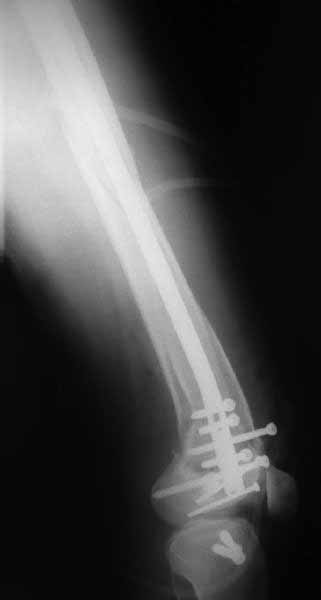

Ответ на эту часть Вашего поста – вложенный файл. Больная оперирована неделю назад по поводу открытого перелома дистального эпиметафиза бедренной кости. После операции она идёт в рентгенкабинет для выполнения послеоперационной контрольной рентгенографии, представленной на слайдах 10 и 11. Узнав, почему её фотографируют, просила передать Вам, Антон, привет.

Позволю себе напомнить коллегам ещё раз, что являюсь сторонником антеградного остеосинтеза при переломах дистального эпиметафиза бедренной кости. Такая приверженность основана не на преимуществах внесуставного введения стержня или большем проценте положительных результатов. Она основана на возможности обеспечить блокирование на минимальном расстоянии от суставной поверхности в нескомпрометированной кости и, таким образом стабилизировать максимально низкие переломы. В приведенном Вами случае самый дистальный из блокирующих винтов проведен на расстоянии более 2 см от конца стержня. Из-за того, что к стержню присоединяется кондуктор, на стержне теряется 1-1,5 см его длины, где можно было разместить отверстия для блокирования. И что более важно, вместе с потерянной для этой цели длиной стержня утрачивается для размещения блокировочных винтов, пожалуй, самая ценная часть дистального эпиметафиза бедренной кости. Проблемы дистального блокирования в разных плоскостях, локализации точки ввода стержня при антеградном остеосинтезе – это всё решаемые технические проблемы. Но антеградный остеосинтез низких дистальных переломов бедра при адекватном блокировании в нескомпрометированной кости обеспечивает решение стратегической задачи – стабильный остеосинтез и возможность нагрузки.